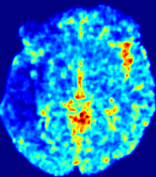

LesionRefer to captionRefer to captionRefer to captionRefer to captionRefer to captionRefer to caption𝐕rgbsubscript𝐕𝑟𝑔𝑏{\bf{V}}_{rgb}Refer to captionRefer to captionRefer to captionRefer to captionRefer to captionRefer to caption𝐕2subscriptnorm𝐕2{\|\bf{V}}\|_{2}Refer to captionRefer to captionRefer to captionRefer to captionRefer to captionRefer to captionRefer to caption3.53.53.52.82.82.82.12.12.11.41.41.40.70.70.70.00.00.0(mm/s)𝑚𝑚𝑠(mm/s)D𝐷DRefer to captionRefer to captionRefer to captionRefer to captionRefer to captionRefer to captionRefer to caption0.0200.0200.0200.0160.0160.0160.0120.0120.0120.0080.0080.0080.0040.0040.0040.0000.0000.000(mm2/s)𝑚superscript𝑚2𝑠(mm^{2}/s)Slice #1Slice #2Slice #3Slice #4Slice #5Slice #6

Figure 3: PIANO feature maps for one stroke patient, where the lesion is located in the left hemisphere. Top row: segmented stroke lesion region (white) on different slices, obtained from ISLES 2017. The corresponding slices for the PIANO feature maps are shown in the following rows.

For a better insight into an estimated velocity field 𝐕𝐕{\bf{V}} and diffusion field 𝐃𝐃{\bf{D}}, we compute the following maps: (1) 𝐕rgbsubscript𝐕𝑟𝑔𝑏{\bf{V}}_{rgb}: Color-coded orientation map of 𝐕=(Vx,Vy,Vz)T𝐕superscriptsuperscript𝑉𝑥superscript𝑉𝑦superscript𝑉𝑧𝑇{\bf{V}}=(V^{x},V^{y},V^{z})^{T}, obtained by normalizing 𝐕𝐕{\bf{V}} to unit length and mapping its 3 components to red, green, blue respectively; (2) 𝐕2subscriptnorm𝐕2\|{\bf{V}}\|_{2}: 222 norm of 𝐕𝐕{\bf{V}}; (3) D𝐷D: scalar field in Eq. 5.

Fig. 3 and Fig. 4 show the PIANO feature maps estimated from two ISLES 2017 patients: all are highly consistent with the lesion in both cases. Details of the blood flow trajectories are revealed in 𝐕rgbsubscript𝐕𝑟𝑔𝑏{\bf{V}}_{rgb} by the ridged patterns and the sharp changes of colors in the unaffected (right) hemisphere, while the flat patterns appearing within the lesion provide little directional information about the velocity and indicate low velocity magnitudes. Velocity magnitudes are more directly visualized via 𝐕2subscriptnorm𝐕2\|{\bf{V}}\|_{2}, from which one can easily locate the lesion where 𝐕2subscriptnorm𝐕2\|{\bf{V}}\|_{2} is low. D𝐷D also indicates lower diffusion values in the lesion, though with less contrast potentially due to the fact that it captures the accumulated effect of CA diffusion at the voxel-level.